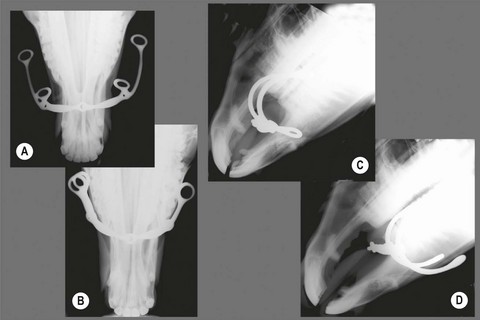

image

Fig. 3.16 Overcheck bits. (A) McKerron with check rein and nose strap. (B) Burch. (C) Crit Davis. (D) Crabb. (E) Hutton. (F) Speedway. (G) Plain. (H) O’Mara leverage.

The plain overcheck bit (Figs 3.16G, 3.17A & 3.19A) is a very small straight bar bit. However, there are many other types, varying widely in severity (Fig. 3.16). Some racing overchecks, like the McKerron (Figs 3.16A & 3.17B), Crit Davis (Figs 3.16C, 3.17C & 3.19B), and Crabb (Figs 3.16D & 3.19C), listed in increasing order of severity, are used in combination with nose straps to prevent horses from leaning into their check reins.1,29 Potentially even more severe is the Burch overcheck (Figs 3.16B & 3.19D), which is shaped so as to press directly into the hard palate.

The cumbersome appearing, but reasonably humane and effective, Raymond and O’Mara (the so-called leverage overchecks) involve no bit at all. (Figs 3.16H & 3.17D) When a horse leans into a leverage overcheck, a strap over his face presses down onto his nose and the U- or V-shaped lower portion of the overcheck lifts up on his chin.1,29

The combination of forces applied by the driving and check reins can place marked stress on a horse’s mouth, and one must be aware of the type of overcheck used when caring for a horse’s teeth and mouth. For example, the hard palate should be examined carefully for injury in a harness-racing horse who performs poorly when checked with a McKerron, Hutton, Burch, Crit Davis, or Crabb bit. If the palate is sore, one should consider recommending a change to a chin chain or leverage overcheck.1

Removal of wolf teeth, careful floating and rounding of the upper premolars and removing sharp edges from upper canine teeth are of special importance whenever overchecks are used.1,30 The upper canines are placed more caudally than the lower canines thus providing less space for the overcheck bit than for the driving bit. The overcheck bit may be forced backwards, especially if the horse’s head is checked very high, pinching the gums against the teeth. Even leverage overchecks can force a horse’s cheeks against upper points or caps.